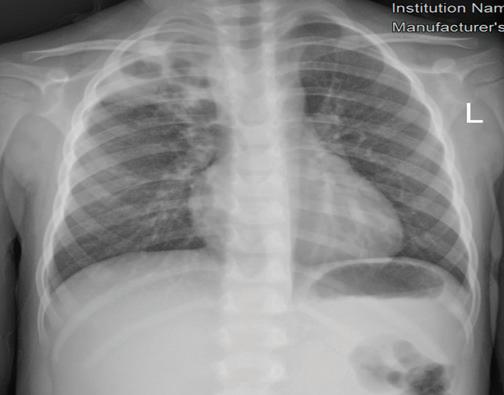

Придобитата в обществото пнев мония (ППО) все още остава чес та причина за заболяемост и смърт ност в световен мащаб. Честотата е най-висока при деца на възраст под 5 години и е от 10 до 40 случая на 1000 деца годишно[1,2]. Изчислено е, че ППО е причина за една пета от смъртните случаи при малки деца, с около два милиона смъртни случая годишно в развиващите се страни и развитият свят.

В световен мащаб S. pneumoniae и H. influenzae са водещите причинители на бактериална пневмония. Най-чес тите патогени, идентифицирани при последното активно наблюдение на населението в Съединените щати, са човешки риновирус, грипен вирус и Streptococcus pneumoniae[4]. Метицилин-резистентен Staphylococcus aureus (MRSA), който първоначално е определян като но зокомиален патоген, все по-често се открива

ност [СПИН] и тежка съпътстваща бе лодробна болест, като бронхиекта зии, кистична фиброза и хронична обструктивна белодробна болест [ХОББ])[8]. Известно е (главно на база та на проучвания на пунктати от бе лите дробове, проведени в развива щите се страни), че леката и умерена ППО се причинява главно от вируси, особено през първите години от жи вота, докато повечето случаи на теж ка ППО се причиняват от бактерии. Въпреки това е доказано, че грипни те вируси и респираторно-синцити алният вирус играят

в общността, където се на рича придобит в общността MRSA. Същият може да доведе до тежки бе лодробни инфекции, включително некротизираща и хеморагична пнев мония[7] Инфекцията с Pseudomonas aeruginosa е рядка при липса на спе цифични рискови фактори (скорош но антибиотично лечение, синдром на придобита имунна недостатъч

основна роля в причиняването на тежка и/или ус ложнена ППО. Значителен брой деца с ППО, причинени от атипични бак терии, показват сложно протичане, поради наличието на плеврален из лив[5] РИСКОВИ ФАКТОРИ И ЗАЩИТНИ МЕХАНИЗМИ НА ОРГАНИЗМА Микроорганизмите са разви ли разнообразни механизми, кои то благоприятстват колонизация та им в гостоприемника. Например, Парапневмонични усложнения – случаи от практиката Ю. Димитрова, Д. Хасанова, И. Цочева Отделение по педи атрия, УМБАЛСМ “Н. И. Пирогов” - София Придобитата в обществото пневмония все още остава честа причина за заболяемост и смърт ност в световен мащаб. Честотата е най-висока при деца под 5 години. S. pneumoniae и H. influenzae са водещите причинители на бактериална пневмония. При деца над 5-годиш на възраст зачестяват атипичните бактериални причинители - Mycoplasma pneumoniae и Chlamydophila pneumoniaе. Най-често тежките пневмонии, които протичат с усложнения, са вследствие на бактериални причинители и се изявяват с парапневмоничен излив, емпиема, мултилобарно заболяване, кавитарен абсцес, некротизираща пневмония, пневмоторакс, и бронхоплеврална фистула. ПЕДИАТРИЯ Ключови думи: Деца, ППО, парапневмонични усложнения.